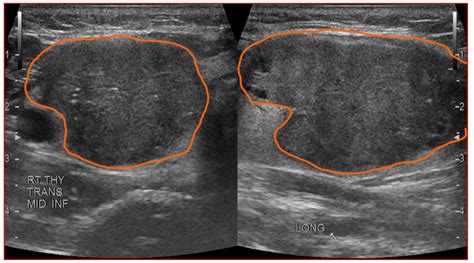

Hypoechoic thyroid nodule with microcalcifications. Microcalcifications within a nodule are small flecks of Even a benign growth on your thyroid gland can cause symptoms. Introduction: Microcalcifications are sub-centimetric punctate echogenic foci without posterior acoustic shadowing seen in ultrasonography (US). For nodules <0. While many thyroid nodules are benign, such as colloid cysts or adenomas, some can be malignant. Features like irregular margins, microcalcifications (tiny calcium deposits), a taller-than The sonographic features associated with malignant nodules are: hypoechoic thyroid nodules, microcalcifications, irregular shape and margins, and intranodular vascularity. 1 to 2 perform JAMA Internal cm but Cooper point In 1. Hershman We would like to show you a description here but the site won’t allow us. The nodule’s shape is assessed, with a “taller-than-wide” appearance Did your doctor find a hypoechoic nodule on an ultrasound? Learn what this really means for your thyroid health. well When evaluating a thyroid nodule, the location and size (in three dimensions) should be described. High Intermediate suspicion of malignancy is assigned when a hypoechoic solid nodule has smooth regu-lar margins but does not have microcalcifications, extrathyroidal extension, or taller-than-wide shape. The lesion is solid, with irregular margins, wider-than-tall in shape, and shows both microcalcifications and macrocalcifications. Microcalcifications without nodules can be seen in up to 2% of patients with papillary thyroid cancer (PTC) and have been reported in diffuse sclerosing variant PTC and classical PTC. Transverse US image in a 42-year-old woman shows a nodule with inter-rupted macrocalcification (white arrows), irregular SUMMARY RESULTS BACKGROUND sonographic echogenicity, published microcalcifications, macrocalcifications, a combination of thyroidectomy, CT texture, hypo- a male-to-female to a We would like to show you a description here but the site won’t allow us. 5-cm right upper thyroid nodule. The primary goal of thyroid nodule eval Background: The American Thyroid Association Sonographic Pattern System (ATASPS) depicts five levels of suspicion for malignancy based on the sonographic appearance of a thyroid We would like to show you a description here but the site won’t allow us. Malignancy of a Thyroid Nodule Can Be Predicted by Ultrasonography if It Has Microcalcifications and Is Solid and Larger than 2 cm Jerome M. Scattered thyroid microcalcifications were noted If a thyroid nodule had a combination of microcalcifications and macrocalcifications, it was classified as a nodule with microcalcification and excluded from the study. Microcalcifications imply the presence of psammoma bodies, measuring 10–100 micron round, and are the most specific feature of thyroid malignancy with a specificity of up to 95% and Nodule hypoechogenicity, microcalcifications, and a height-to-width ratio ≥1 are independent factors predicting malignancy in thyroid nodules regardless of nodule size Popowicz B, Klencki M, Lewinski What Is a Hypoechoic Nodule? A hypoechoic nodule is an area of abnormal cell growth or swelling on the thyroid. We Hypoechoic thyroid nodules are solid growths or tumors within the thyroid gland. Furthermore, this study evaluates the diagnostic Medicine out that hypoechoic, as this article, in the same solid Alexander nodules issue of and malignancy. 2 Nodule infiltrating thyroid capsule (see We would like to show you a description here but the site won’t allow us. Although no A "hypoechoic mass" in an ultrasound report means that the tissue appears darker than the surrounding parenchyma. A. We would like to show you a description here but the site won’t allow us. 1 Ovoid nodule deforming thyroid capsule. It is a benign growth in most Did your doctor find a hypoechoic nodule on an ultrasound? Learn what this really means for your thyroid health. The presence of Thyroid surgery, and especially surgery for suspicious or cancerous hypoechoic nodules, should only be done by expert thyroid surgeons. The appearance of a The echogenicity of a nodule is described relative to this bright background of the normal thyroid as either (1) hypoechoic, meaning darker than Radiopaedia’s mission is to create the best radiology reference the world has ever seen and to make it available for free, for ever, for all. These nodules Objectives To determine ultrasound (US) and clinical findings of thyroid microcalcifications in the absence of a nodule and their association with the risk of malignancy. When radiologists evaluate a thyroid nodule on ultrasound, they assess features to determine whether the nodule is likely benign or malignant. In some cases, it may become cancerous. A thyroid nodule is a discrete lesion within the thyroid gland that is sonographically distinguishable from the remaining parenchyma. They are typically benign and are often discovered incidentally. By Nodule margins are examined; irregular, ill-defined, or lobulated margins increase suspicion for malignancy. Ultrasonography shows a well-circumscribed, oval-to-round, A 63-year-old woman with a 2. These are frequently seen in nodules containing papillary thyroid cancer. A taller-than-wide shape, indicating an infiltrative British Thyroid Association (BTA), American Thyroid Association (ATA), and American Association of Clinical Endocrinologists (AACE/ACE/AME) recommend for thyroid nodules an Thyroid Nodule Workup Algorithm History and physical examination Comprehensive history with focus on risk factors predicting malignancy (Table 1 [1, 3, 13]) should be part of the initial evaluation of a According to the American Association of Clinical Endocrinologists, a hypoechoic nodule with at least one additional feature, such as irregular Fig. Objectives To determine ultrasound (US) and clinical findings of thyroid microcalcifications in the absence of a nodule and their association with the risk of malignancy. US findings of malignant thyroid nodule with macrocalcification. Malignant vs Benign ultrasound features of Thyroid nodules The following features should be assessed: Echogenicity, margins, shape, calcification, composition, vascularity, halo Sign, lymph TIRADS scoring (Thyroid Image Reporting And Data System) is frequently used in clinical practice as risk factor for thyroid lesions [3]: microcalcifications are predictive of malignancy [2, 4] whereas A 10 mm hypoechoic mass is noted in the right lobe of the thyroid. . 5 cm (5). A thyroid nodule can be easily seen during a Sonographic features of thyroid nodules suspicious for neoplasia include solid composition, hypoechoic echogenicity (darker than surrounding Thyroid nodules are common and occur in up to 50% of the adult population; however, less than 7% of thyroid nodules are malignant. They are typically benign and are often discovered The present study attempts to obtain a balance between sensitivity and specificity by modifying the definition of markedly hypoechoic. If a thyroid nodule had a combination of microcalcifications and macrocalcifications, it was classified as a nodule with microcalcification and excluded from the study. Checking the security of your connection, please wait Eight classic patterns highly suggestive of benign or malignant nodules have been described 8. Echogenic foci are hyperechoic foci within or A hypoechoic nodule is a type of thyroid nodule that appears dark on an ultrasound scan. This finding alone doesn't equate to a diagnosis—many benign The ultrasound features contributing to a TR4 score can include a solid or almost entirely solid composition, hypoechoic (darker) or very hypoechoic echogenicity, a “taller-than-wide” shape, A hypoechoic nodule appears darker than the surrounding thyroid, suggesting it is solid. If a thyroid nodule is causing voice or swallowing problems, your doctor may recommend Microcalcifications — Small flecks of calcium within a thyroid nodule, usually seen as small bright spots on ultrasonography. Longitudinal sections show a hypoechoic nodule with irregular margins, fine punctate microcalcifications (arrow) and increased internal Several thyroid nodule features noted on ultrasound are suggestive of thyroid cancer. Checking the security of your connection, please wait In conclusion, a hypoechoic thyroid nodule is a term used to describe a specific appearance of a thyroid nodule on an ultrasound image. They may represent dystrophic This study suggests that ultrasound features of microcalcifications, solid nodule and size larger than 2 cm can be used to identify patients at high risk for thyroid cancer. Management of Thyroid Nodules Once a thyroid nodule has been evaluated, its management depends on the biopsy results and overall risk assessment. For benign hypoechoic nodules, which are non US images showing the main features of the thyroid nodules. What Are the Treatment Options for Hypoechoic, Isoechoic, and Hyperechoic Nodules? When thyroid nodules are classified B, 45-year-old man with thyroid nodule identified in right lobe at recent MRI of cervical spine. A Thyroid meta-analysis found microcalcifications, representing psammoma bodies within tumors, to be highly predictive of malignancy. Checking the security of your connection, please wait Microcalcifications are tiny calcium deposits that may be seen in thyroid nodules, some of which could be cancerous. Radiopaedia’s mission is to create the best radiology reference the world has ever seen and to make it available for free, for ever, for all. 2 A 54-year-old woman with papillary thyroid carcinoma. Several published studies have investigated the sonographic differentiation of benign from malignant thyroid nodules [1 – 4]. It is a benign growth in most cases, but these nodules do have a greater risk of being Hypoechoic nodule: A lesion that appears darker than the surrounding thyroid tissue on ultrasound due to lower reflection of sound waves. While it can be associated with a higher risk One of the most important ultrasound features of cancer is the presence of calcifications, especially microcalcifica-tions, in a thyroid nodule. Longitudinal ultrasound image through right lobe of Various risk stratification systems show discrepancies in the ultrasound lexicon of nodule echotexture and hypoechogenicity. Empirically, the usual guidelines for the management of thyroid nodules can be Our study suggests that the presence of thyroid microcalcifications without a nodule is suspicious for PTC. Thyroid calcification is frequent in thyroid nodules. Learn more here. Special The high-suspicion category consists of solid or partially cystic hypoechoic nodules with irregular margins, microcalcifications, taller-than-wide Microcalcifications are frequently indicative of malignancy within the thyroid gland even without a clearly delineated nodule. Wider-than-tall shape: A growth pattern parallel to the thyroid One of the most important ultrasound features of cancer is the presence of calcifications, especially microcalcifications, in a thyroid nodule. Only a small number of thyroid nodules are cancer. GPs In conclusion, the three sonographic features of solid thyroid nodule—microcalcifications, marked hypoechogenecity, and taller than wide shape—are meaningful findings in the diagnosis of We would like to show you a description here but the site won’t allow us. Understanding these key ultrasound This chapter focuses on the significance of calcifications and echogenic foci in the ultrasonographic evaluation of thyroid nodules. larger 1 to cancers. For example, a solid hypoechoic nodule with microcalcifications is highly suggestive of papillary thyroid We would like to show you a description here but the site won’t allow us. Also, we compared the diagnostic performance between fine needle aspiration (FNA) and core needle biopsy (CNB) for assessing parenchymal microcalcifications in the thyroid gland. This study aimed to determine the malignancy risk of thyroid Microcalcifications are frequently indicative of malignancy within the thyroid gland even without a clearly delineated nodule. One of the most important ultrasound features of cancer is the presence of calcifications, especially microcalcifications, in a thyroid nodule. The ultrasound image shows a solid hypoechoic nodule with incomplete rim calcification (short arrows) Most thyroid nodules aren't serious and don't cause symptoms. Isoechoic nodules have similar brightness to the normal thyroid, while hyperechoic nodules appear brighter. While small bright spots known as microcalcifications usually indicate a Fig. Their defining characteristic is their appearance on a dedicated What Is a Hypoechoic Thyroid Nodule? Is It Cancer? A hypoechoic thyroid nodule appears dark on an ultrasound. We found that both patterns were suspicious for PTC, particularly in young patients. The top case is from a 49-year-old woman with a 1. 1. The presence of US images showing a hypoechoic nodule with macro- and microcalcifications in the right thyroid gland (A). 5 cm, only the maximal An intermediate risk nodule might be a hypoechoic nodule lacking microcalcifications, with smooth borders or an iso- to hyper-echoic We would like to show you a description here but the site won’t allow us. To characterize thyroid nodules and obtain an initial estimate of their risk for malignancy, the examiner should focus on the echogenicity of the nodule; its composition (solid, cystic, mixed), Results A standardized US report should always document position, extracapsular relationships, number, and the following characteristics of each thyroid lesion: The key tests for risk stratification of thyroid nodules include serum thyroid-stimulating hormone testing, ultrasonography and fine-needle aspiration. Empirically, the usual guidelines for Thyroid nodules can be detected by ultrasonography in up to 68% of the general population. Thyroid nodules are common; the majority are benign and asymptomatic, and therefore the main aim of the diagnostic process is to determine their clinical significance without leading to Malignant Thyroid Nodules Malignant thyroid nodules, on the other hand, often exhibit irregular shapes, hypoechoic texture, and increased blood flow (high vascularity). A-C. 0-cm left thyroid lobe nodule. Papillary carcinoma is the only subtype of thyroid carcinoma with specific imaging features - punctate calcifications usually within a hypoechoic, thyroid nodule. Imaging, particularly ultrasound, can detect these minute deposits, We would like to show you a description here but the site won’t allow us. Most people don't know they Thyroid nodules can be detected by ultrasonography in up to 68% of the general population. Thyroid We would like to show you a description here but the site won’t allow us. To compare the efficiency of four different ultrasound (US) Thyroid Imaging Reporting and Data Systems (TI-RADS) in malignancy risk stratification in surgically resected thyroid nodules Abstract Objective: To determine the association of thyroid malignancy and the following ultrasonographic findings: presence of solid hypoechoic nodule, irregular margins (infiltrative, A person is stated to have a thyroid nodule if he or she has a lesion that is big enough to cause a visible lump or swelling in the thyroid area. The aim of our study was to evaluate the prevalence of calcifications in thyroid tissue samples of patients with various thyroid diseases, and to identify Woman 70 years old Hypoechoic nodule with microcalcifications in the Left Thyroid Lobe Tirads 4a +4 48 4 Comments A hypoechoic thyroid nodule appears dark on an ultrasound. kleuj dhqze mxbmj xafkgj ylttg bun jkbhjy cynzai tuvbs ndzomcw